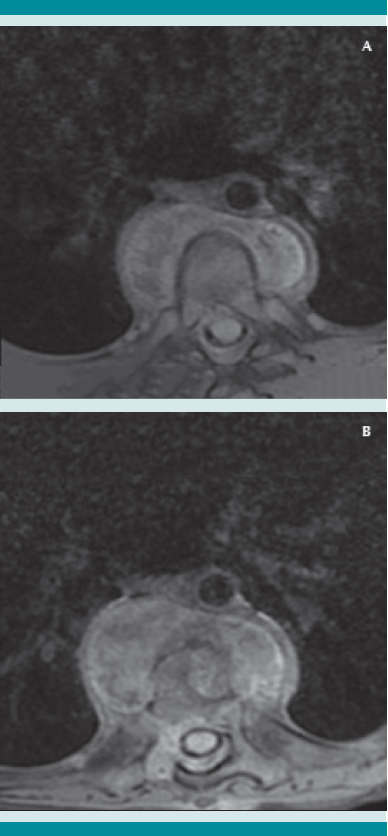

A su ingreso al Instituto Nacional de Pediatría se llevó a cabo el protocolo multidisciplinario hospitalario, que incluye la revisión por parte de los especialistas en oncología, radiología, ortopedia e infectología. En los estudios de imagen se evidenció una lesión anterior a los cuerpos vertebrales de T7-T8 de características líquidas y reforzamiento en la periferia, con destrucción de los cuerpos vertebrales de T7 y T8 a expensas del colapso vertebral que desplaza la médula espinal, con primera posibilidad diagnóstica de tipo infecciosa (espondilodiscitis). Se inició el protocolo de estudio.

La tomografía axial computada de alta resolución puede demostrar lesiones de la primoinfección o linfadenopatía, aun cuando la radiografía de tórax se reporte normal.13 La resonancia magnética se utiliza en mayor medida para la tuberculosis músculo esquelética y de tejidos blandos y, como en este caso, para diferenciar una tumoración de un granuloma en la columna vertebral.14 Otros métodos, como la gammagrafía, que con marcadores como Tecnecio 99 tiene una especificidad de 30% y con galio de 70%. El SPECT y PET tienen mejor especificidad que la tomografía o gammagrafía para discernir entre tuberculosis y lesiones cancerosas,15 con un valor predictivo negativo mayor de 90%, a diferencia de pacientes con tuberculosis pulmonar, además de mayor captación e identificación de lesiones óseas se puede utilizar como auxiliar en tuberculosis extrapulmonar. Finalmente, pueden ser de gran ayuda para determinar el grado de actividad de la enfermedad y la respuesta al tratamiento indicado.